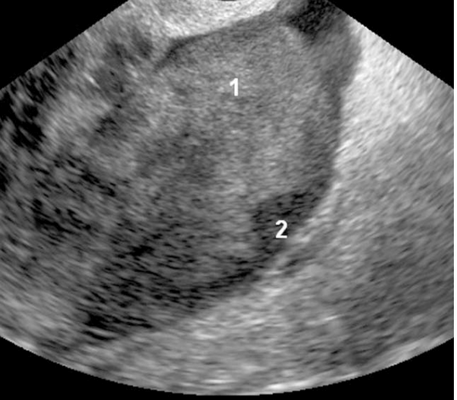

Рис.2. Метастазы колоректального рака: многокамерная-солидная опухоль с типичной округлой формой (2) с папиллярными разрастаниями из перегородок (1).

Типичными признаками метастазов колоректального рака были: округлая форма каудальной части опухоли, наличие папиллярных разрастаний и наличие некроза твердой части. Опухоли были преимущественно с гиперэхогенными перегородками в основном с гипоэхогенной или гетерогенной твердой частью. Имеющиеся папиллярные разрастания от изоэхогенных до гиперэхогенных, растущих из тонких перегородок и являющихся специфическими для метастазов колоректального рака, наблюдались у 5/32 (15,6%) опухолей (рис.2).